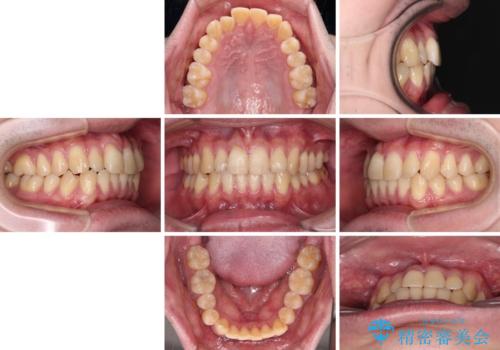

【モニター】前歯のデコボコとクロスバイト ワイヤー矯正で短期間に仕上げる

- 前歯のデコボコとクロスバイトを気にして来院された患者様です。

インビザラインでもワイヤー装置でも矯正治療は可能でしたが、煩わしい自己管理なしに短期間で治療を行いたいとのことで、目立たないワイヤー装置にて治療を行うこととしました。

- 治療費の目安: 85万円(税込)費用は治療当時の料金となります